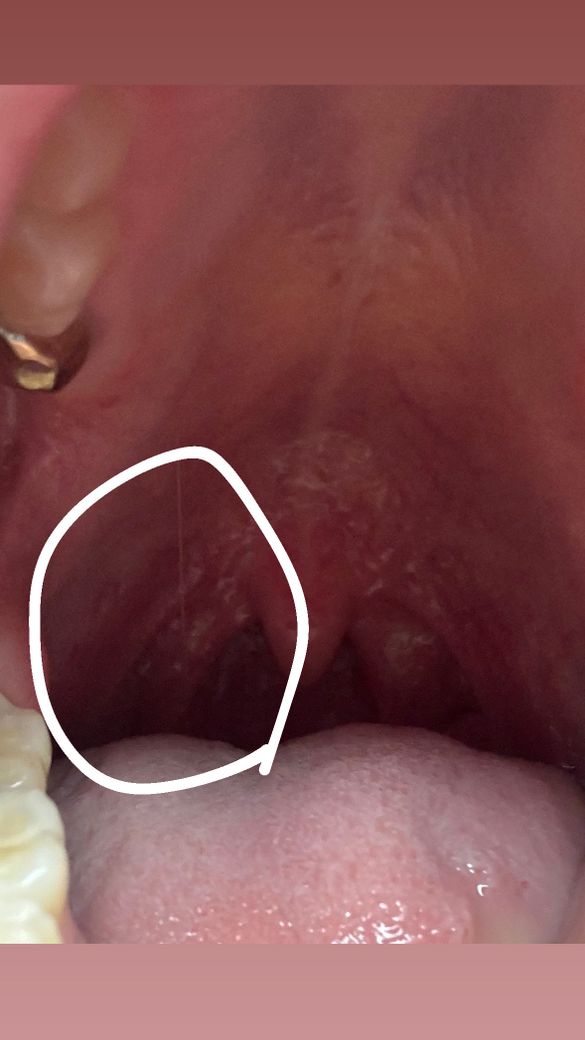

입천장 쪽 혹이 느껴지는데 사진 봐주세요ㅠㅠ

약 1년 전부터 왼쪽 입천장 쪽에 혹이 혀로 느껴지는데

육안으로는 잘 안보이고 도드라져 보이지 않아요 통증이나 크기변화는 없구요..첫 구강성교 후 2-3일만에 생긴게 오래 지속중이에요.. 보기에 이상이 있나요?

사진상으로 크게 문제가 잇어 보이는건 없는거 같습니다. 편도가 약간 부어 잇는거 같으니 이비인후과도 한번 가보세요.

사진으로 봐서는 명확히 알기 어렵습니다 정확한 검사를 위해 대학병원 구강내과가보시기 바랍니다